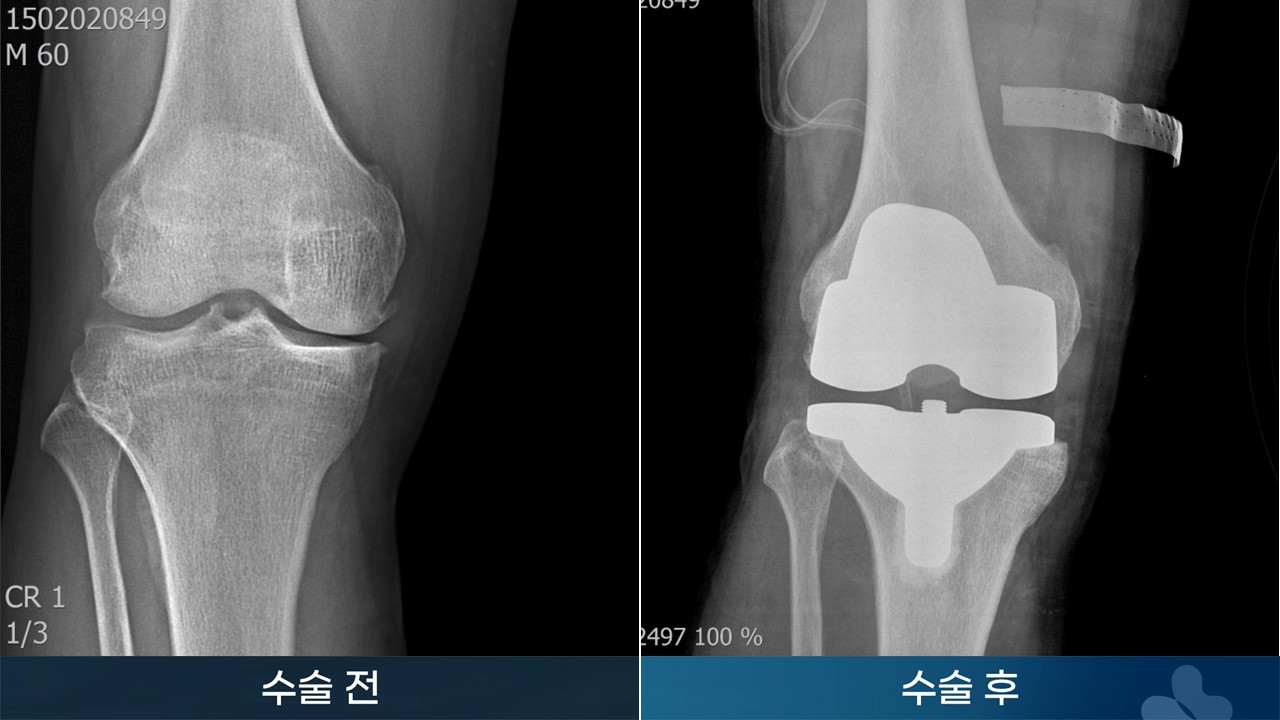

인공관절 슬관절 치환술

e382e32bd76d9.jpg